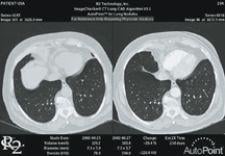

R2’s Version 2.1 ImageChecker CT Lung CAD System for tracking lung nodule growth between current and prior multislice CT exams can now be sent to a PACS workstation for full enterprise accessibility without the need for R2’s dedicated CT CAD workstation. According to the manufacturer, with the new V2.1 software, R2’s Pulmonary Artery Patency Exam (PE) tool features a new algorithm to aide physicians in more effectively detecting intravascular filling defects, such as pulmonary embolism, during review of multislice CT exams.